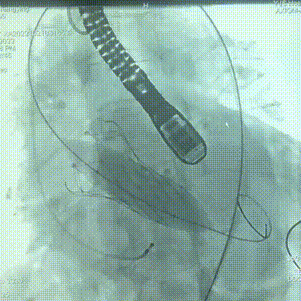

同侧Snare协助下成功将TAV21mm微创瓣膜支架系统沿导丝送达主动脉瓣狭窄处,定位满意后起搏160bpm,缓慢释放支架系统。

瓣膜定位

定位释放

完全释放

起搏160bpm后先后使用20m*40mm瓣膜球囊扩张导管后扩张支架瓣膜。

20x40mm球囊后扩